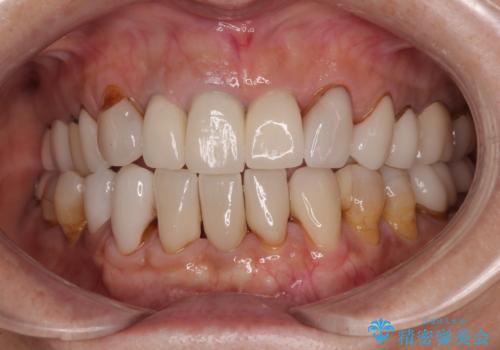

- 前歯のセラミックが欠けたり色調が不揃いであったりすることを気にして来院された患者様です。

20年以上前から、むし歯になったり詰め物が欠けたりする度に部分的に処置を行ってきたそうですが、この際統一感のある前歯にしたいとのことで、上顎前歯9本をオールセラミッククラウンによる補綴治療を行うこととしました。

色調が統一されるだけでなく、歯肉ラインに見えていた茶色の境目も綺麗に改善されました。